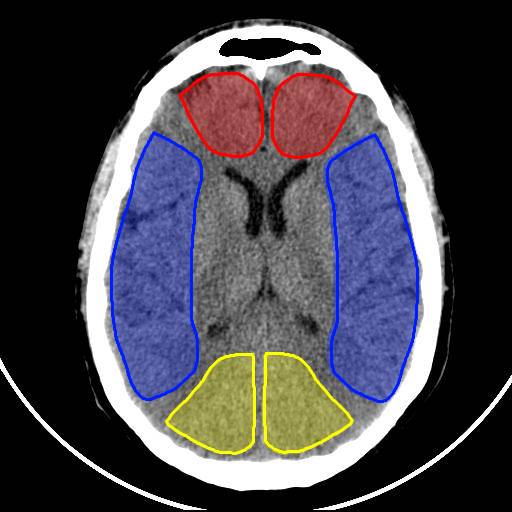

Analyse quantitative

Territoire de l’artère cérébrale moyenne